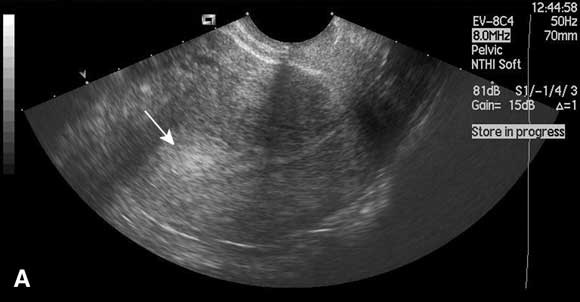

Saline infusion sonohysterography

In this technique, saline is instilled transcervically into the uterine cavity to distend the uterus and increase contrast, and the cavity is visualised using ultrasound (Box). Saline infusion sonohysterography is more accurate than transvaginal ultrasound alone in diagnosing submucous fibroids and endometrial polyps in women with abnormal uterine bleeding,12 and can be performed in the outpatient clinic. An alternative form of imaging is diagnostic hysteroscopy, but this is invasive and often performed under general anaesthesia. Use of saline infusion sonohysterography has been shown to reduce the need for diagnostic hysteroscopy.13